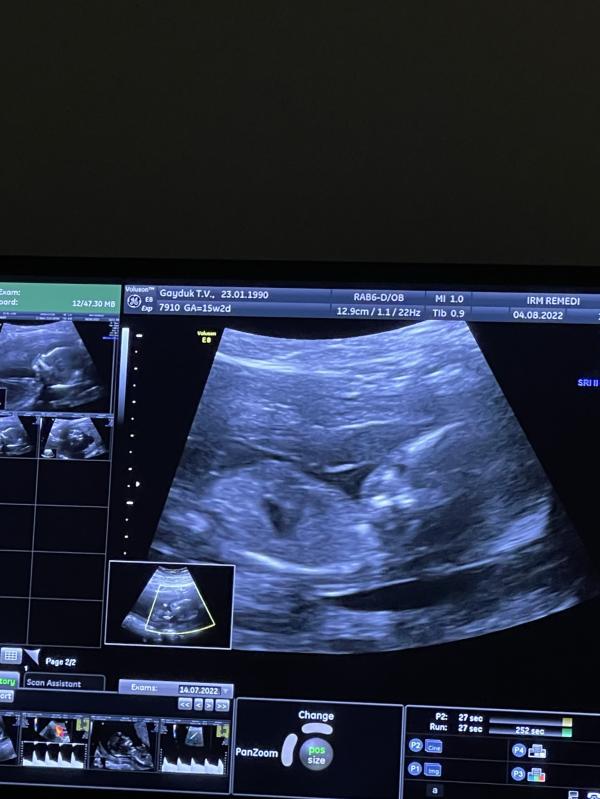

Все скрининги, узи - все великолепно. Никаких нареканий к человечку не было.

По всем УЗИ и 1 скринингу - все отлично. Сейчас расскажу.

По времени сама процедура занимает 3 минуты. Делали под контролем узи. Это НЕ БОЛЬНО!